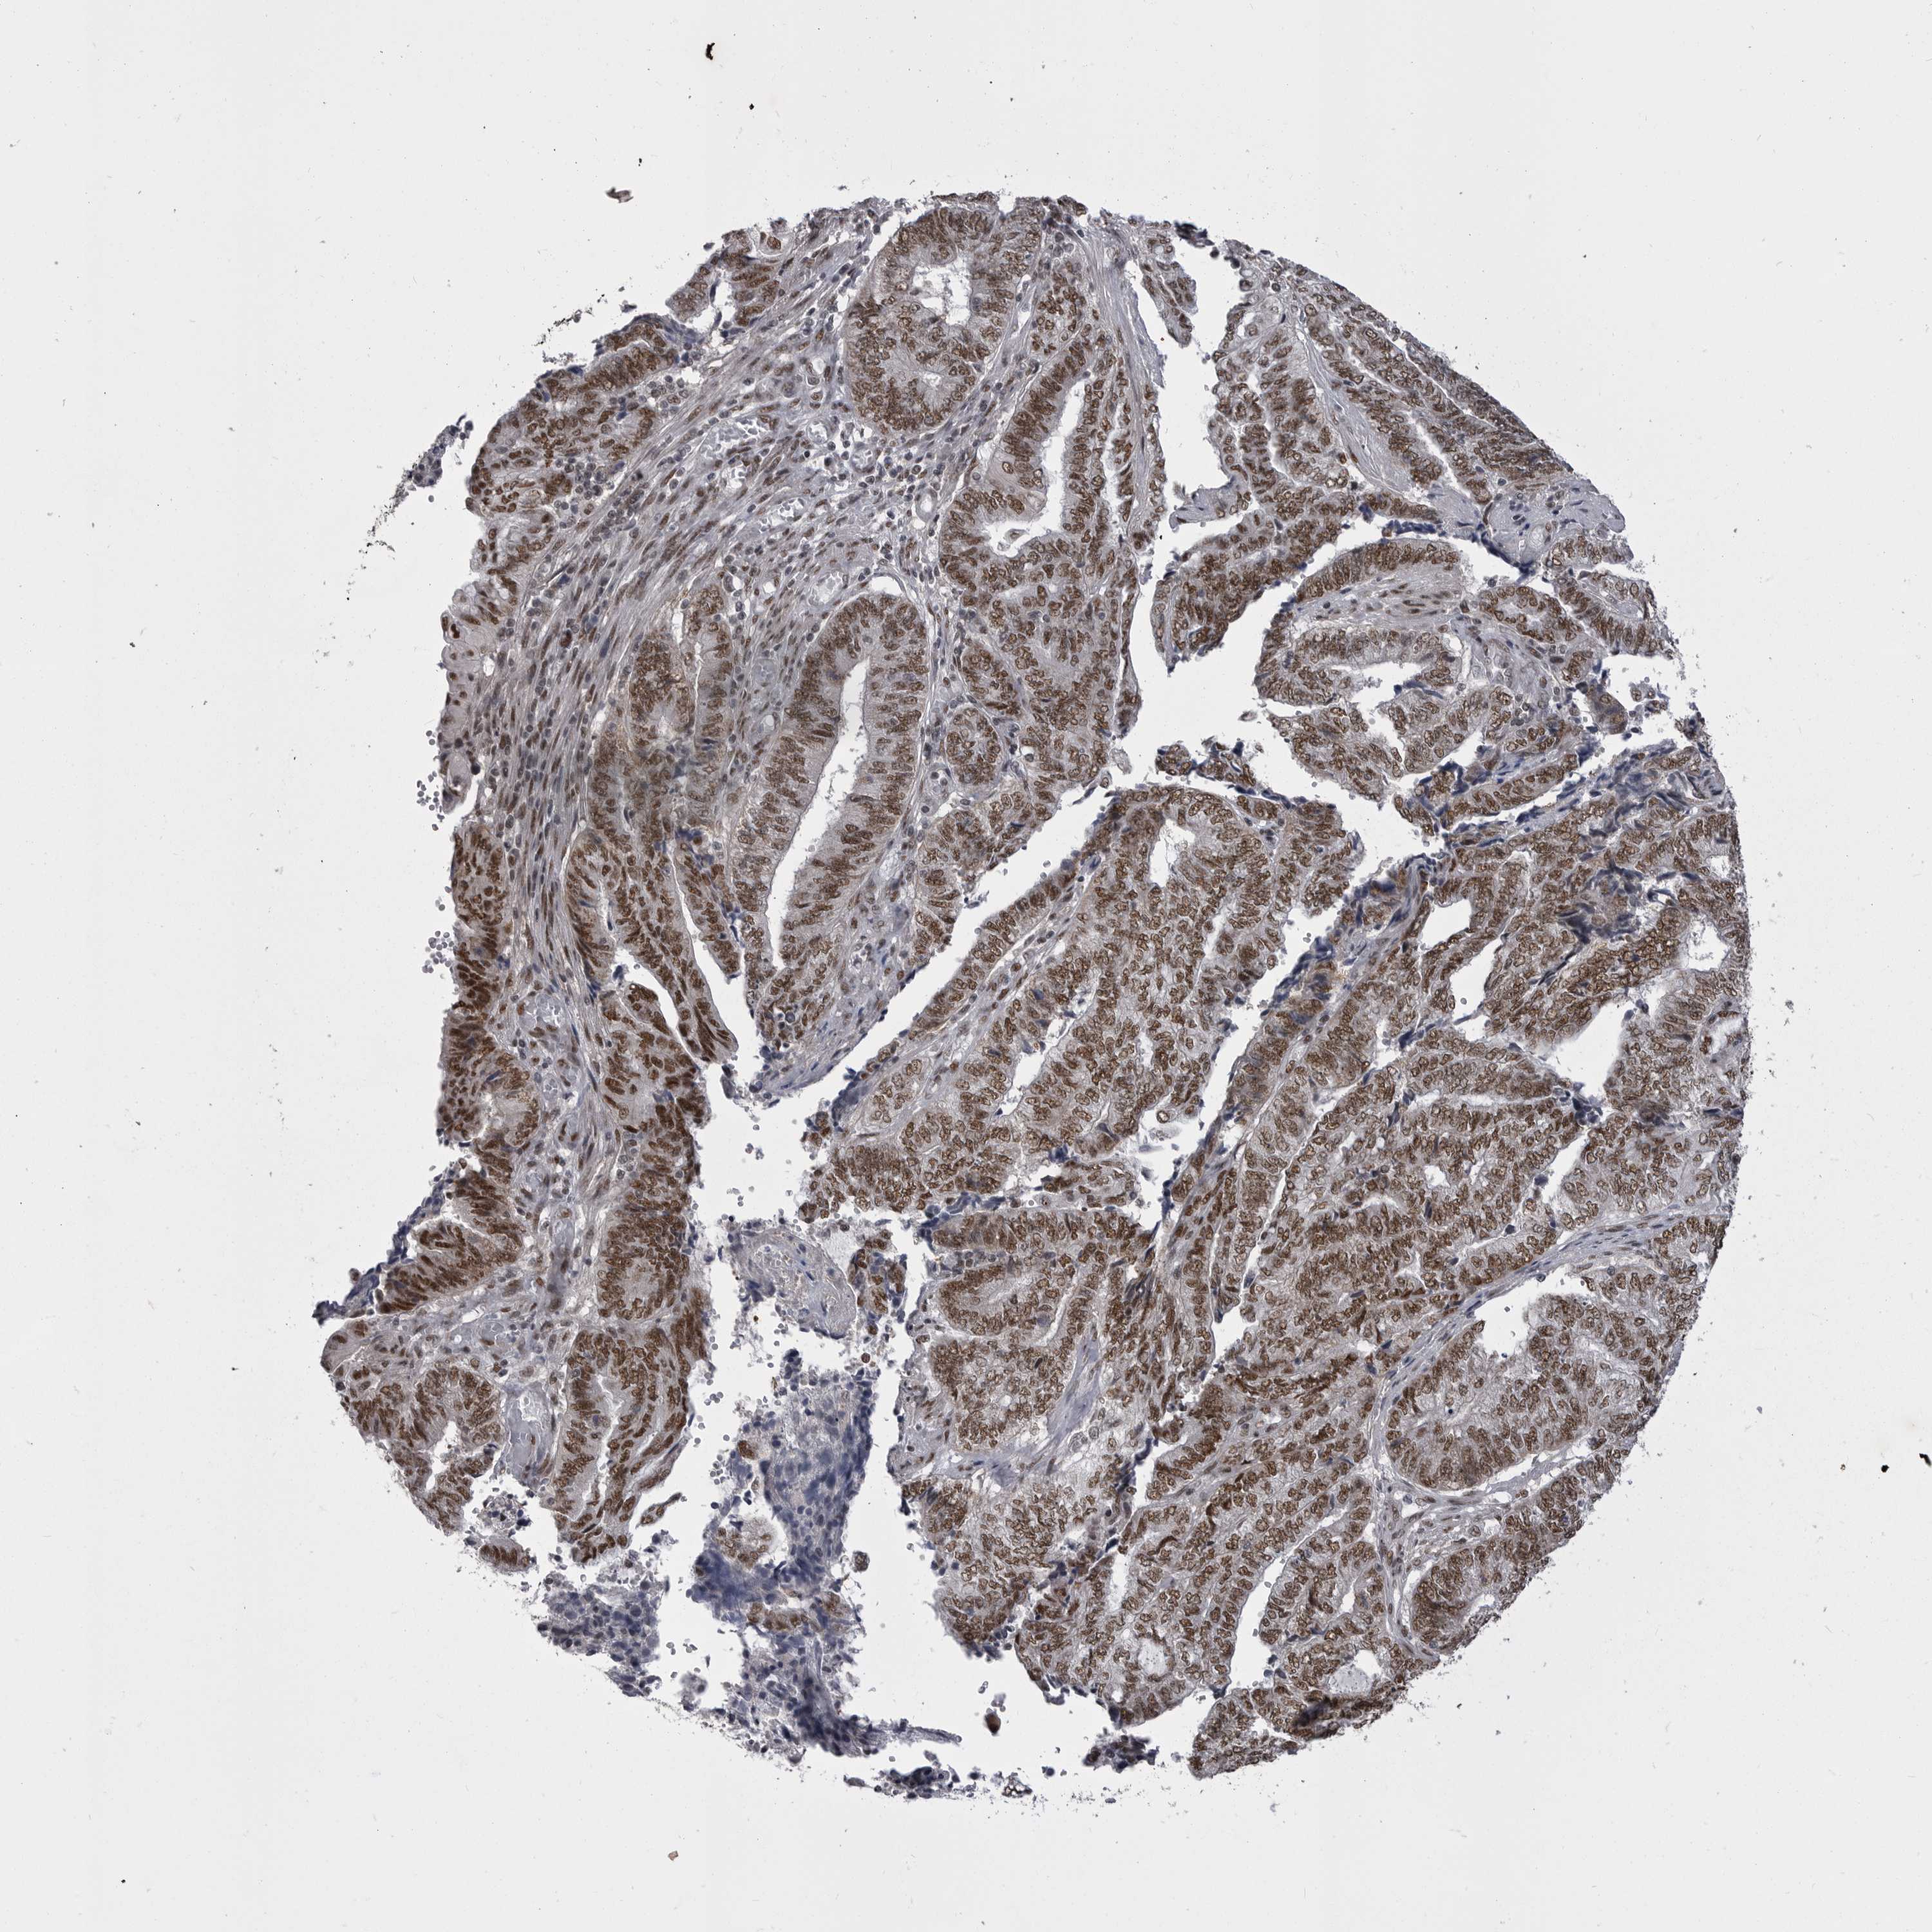

ENDOMETRIAL CANCER - Protein expressioni

A mouse-over function shows sample information and annotation data. Click on an image to view it in a full screen mode. Samples can be filtered based on level of antibody staining by selecting one or several of the following categories: high, medium, low and not detected. The assay and annotation is described here.

Note that samples used for immunohistochemistry by the Human Protein Atlas do not correspond to samples in the TCGA dataset.

Antibody stainingi

Antibody staining in the annotated cell types in the current human tissue is reported as not detected, low, medium, or high, based on conventional immunohistochemistry profiling in selected tissues. This score is based on the combination of the staining intensity and fraction of stained cells.

Each image is clickable and will lead to virtual microscopy that enables deeper exploration of all samples and also displays staining intensity scores, fraction scores and subcellular localization as well as patient and tissue information for each sample.

Antibody HPA051587

Antibody CAB026384

Staining

High

Medium

Low

Not detected

Intensity

Strong

Moderate

Weak

Negative

Quantity

>75%

75%-25%

<25%

None

Location

Nuclear

Cytoplasmic/membranous

Cytoplasmic/membranous,nuclear

Adenocarcinoma, NOS

Carcinoma, NOS

Adenocarcinoma, metastatic, NOS